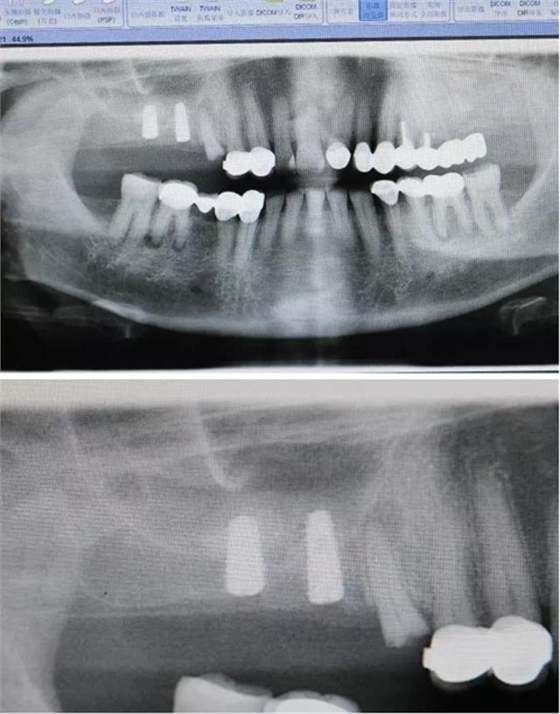

北京種植牙醫(yī)聯(lián)盟特聘講師原解放軍272醫(yī)院口腔科主任2000年開展種植牙專業(yè),年種植量1000顆以上;韓國(guó)DIO種植系統(tǒng)外科培訓(xùn)講師;韓國(guó)DENTIS種植系統(tǒng)外科培訓(xùn)講師;韓國(guó)DIO系統(tǒng)、DENTIS系統(tǒng);種植后上部結(jié)構(gòu)修復(fù)指導(dǎo)老師;北京種植牙醫(yī)聯(lián)盟理事長(zhǎng);國(guó)際種植牙醫(yī)協(xié)會(huì)(ICOI)會(huì)員。